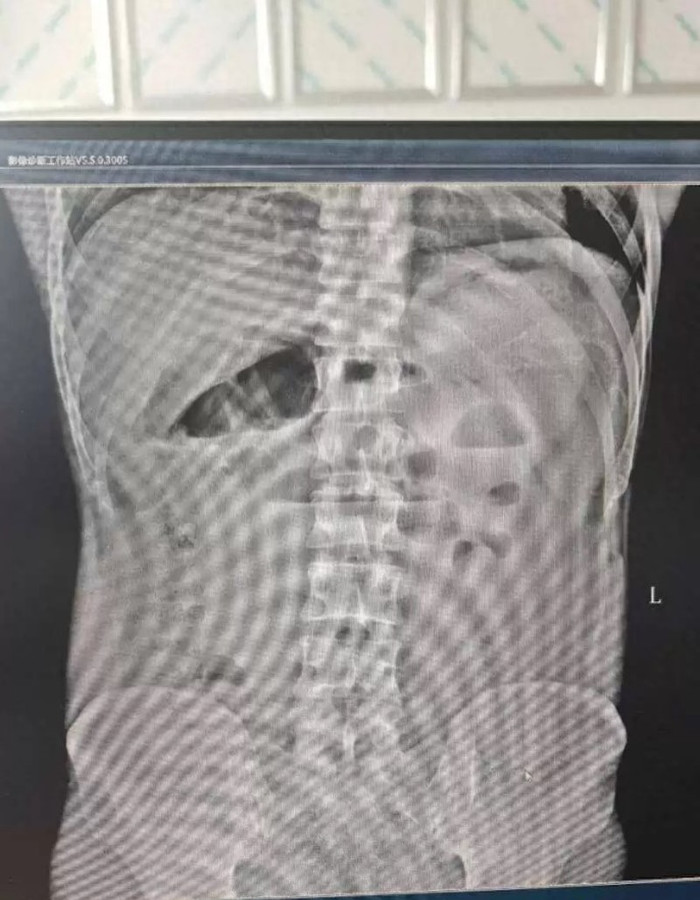

Kết quả chụp CT bụng khiến các bác sĩ không khỏi bàng hoàng. Con lươn đã không chỉ chui vào mà còn khoan thủng đại tràng sigma của bệnh nhân, khiến nó "bơi" tự do trong khoang bụng. Toàn bộ vùng bụng của người đàn ông cứng đơ như gỗ, đau đớn không thể chịu đựng được. Đây là triệu chứng nguy hiểm của viêm phúc mạc lan tỏa, một biến chứng nghiêm trọng có thể dẫn đến sốc nhiễm trùng và tử vong bất cứ lúc nào.